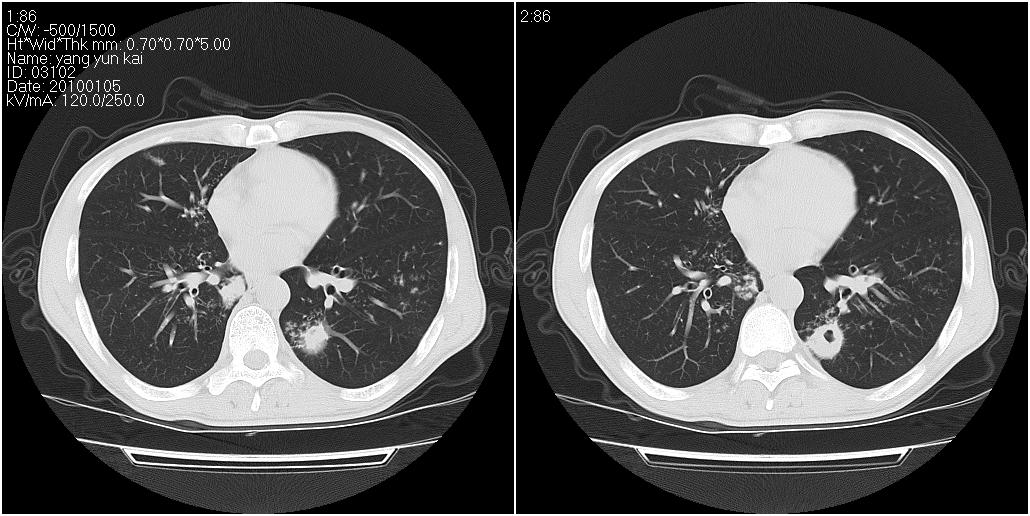

男性,47岁。近来咳痰、咳血,血沉增快(40左右),痰中未检出结核杆菌。

两肺继发性肺结核并多发性结核球形成,部分病灶内空洞形成。